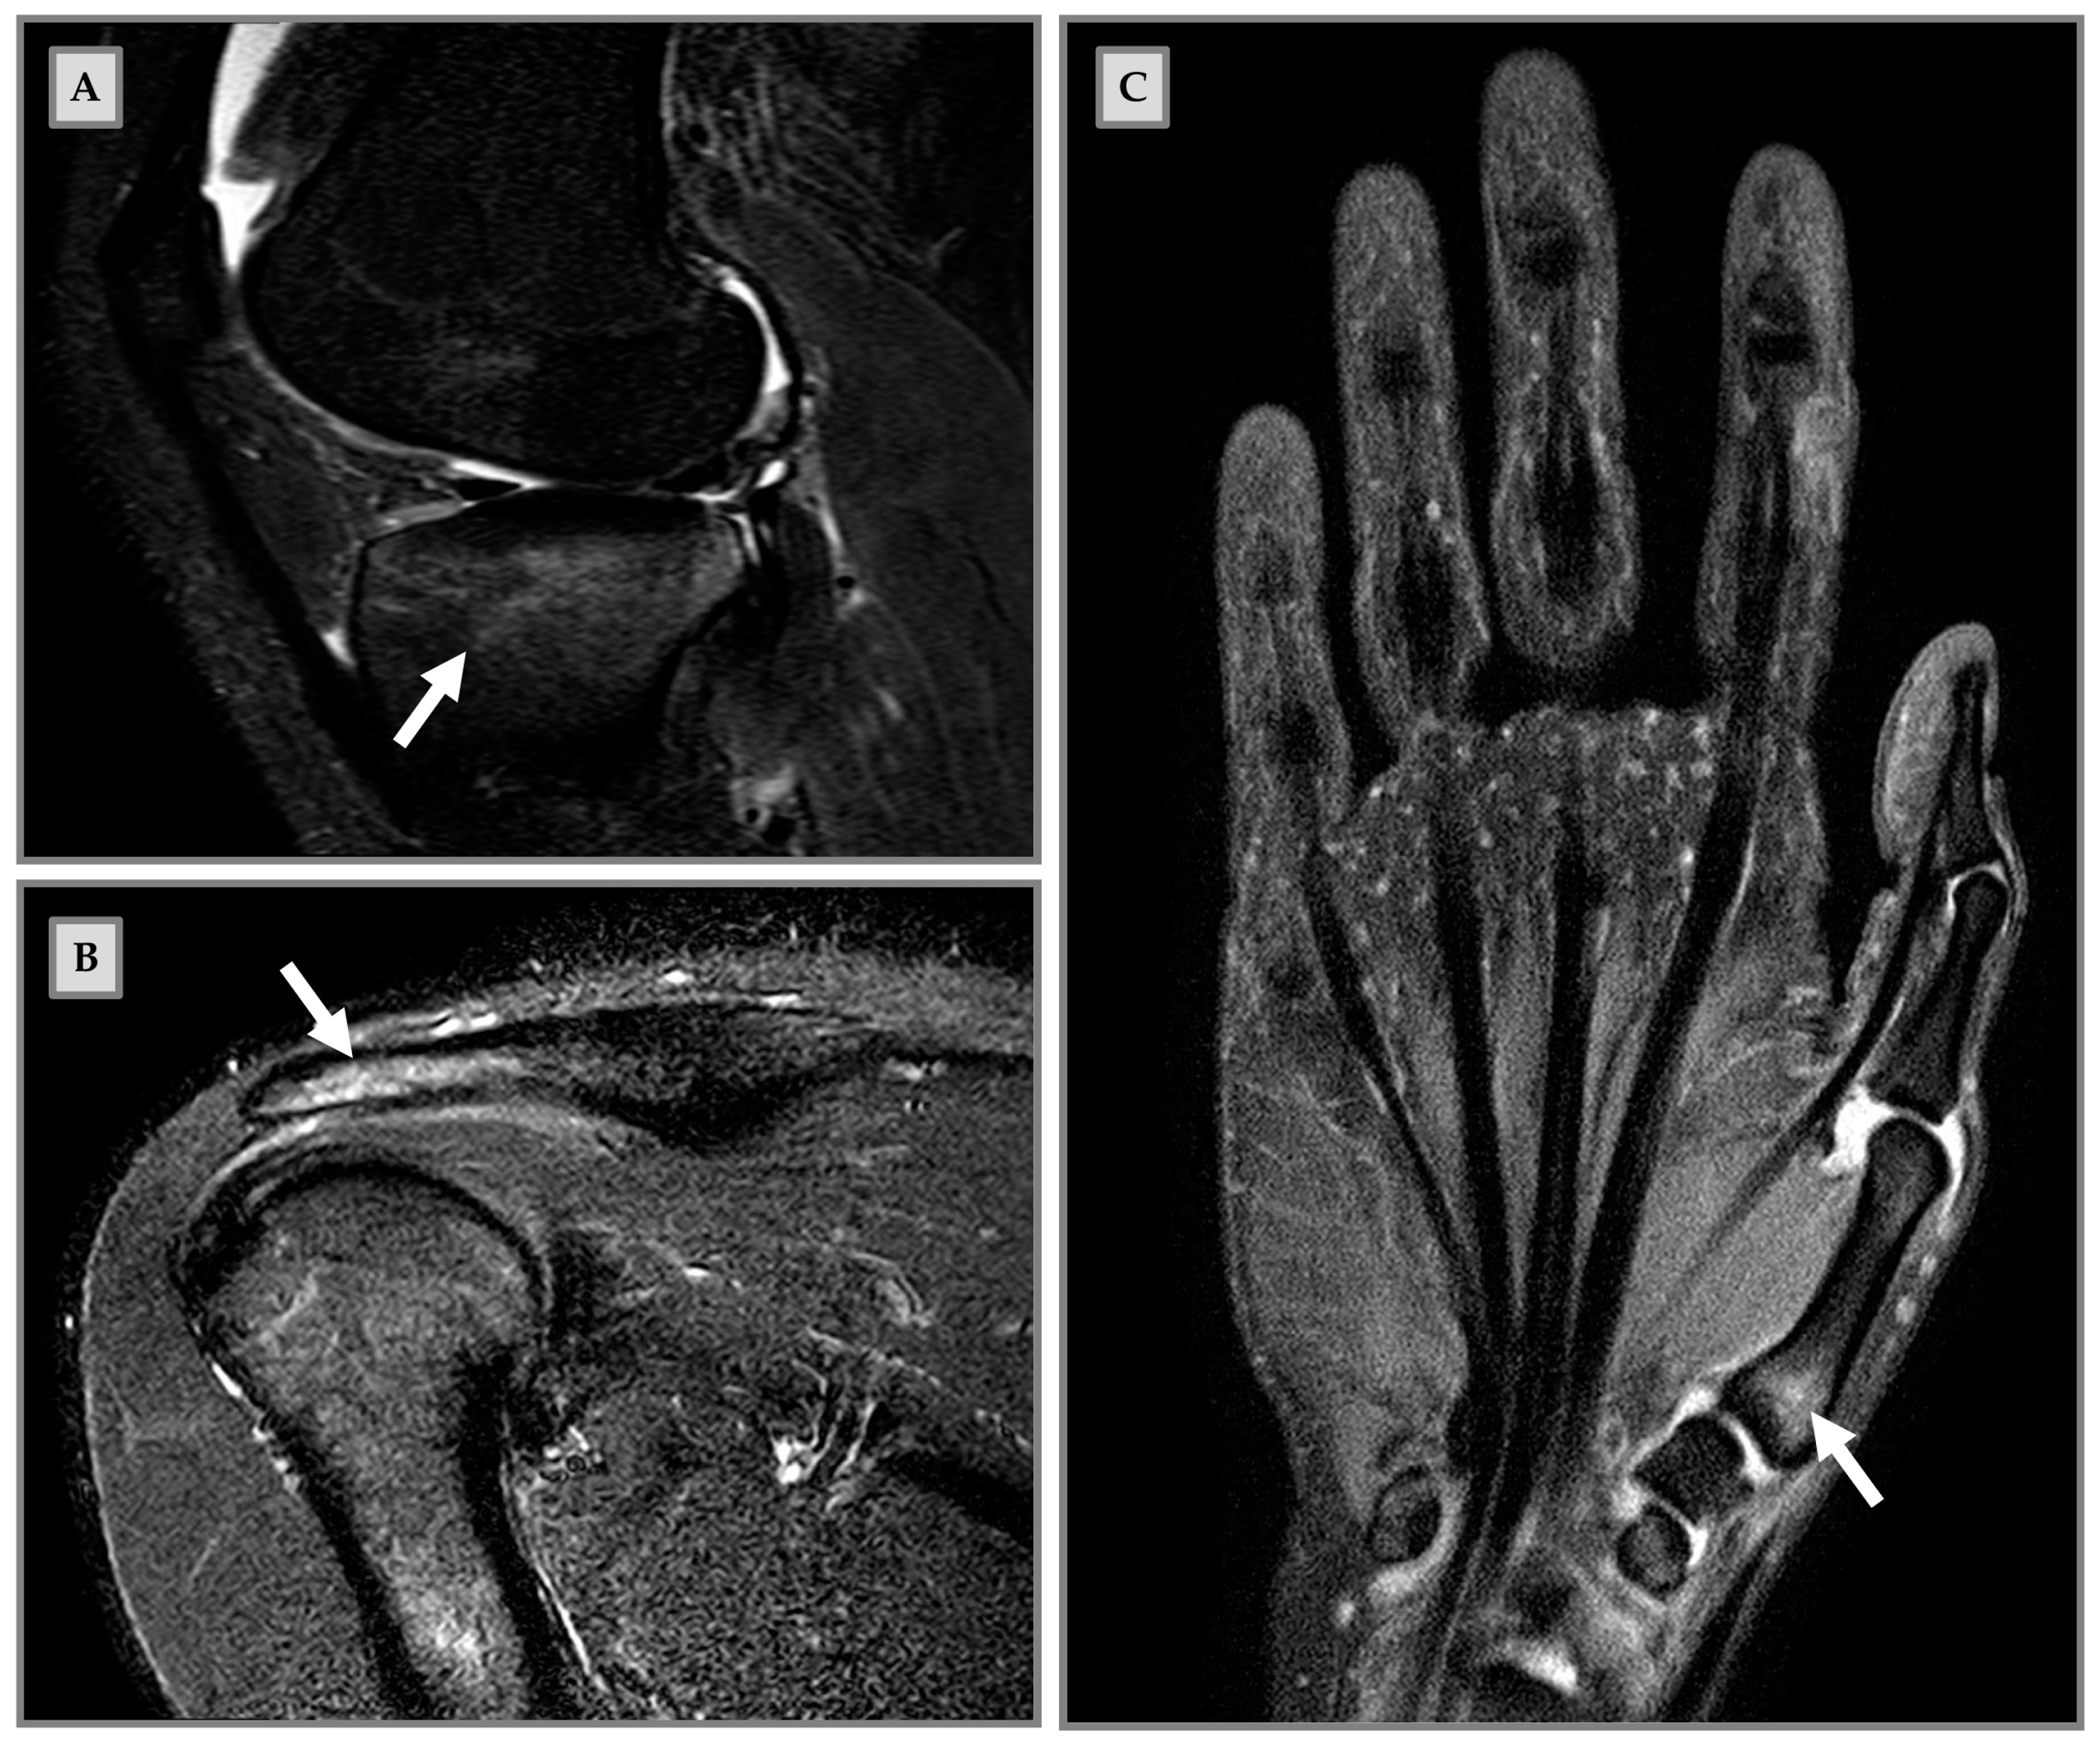

- Grampp, S.; Henk, C.B.; Mostbeck, G.H. Overuse Edema in the Bone Marrow of the Hand: Demonstration with MRI. J. Comput. Assist. Tomogr. 1998, 22, 25–27. [Google Scholar] [CrossRef] [PubMed]

- Kornaat, P.R.; Van De Velde, S.K. Bone Marrow Edema Lesions in the Professional Runner. Am. J. Sports Med. 2014, 42, 1242–1246. [Google Scholar] [CrossRef]

- Mandalia, V.; Williams, C.; Kosy, J.; Brown, K.; Schranz, P.; Redfern, A.; Silver, D.; Powell, R. Bone Marrow Oedema in the Knees of Asymptomatic High-Level Athletes: Prevalence and Associated Factors. Indian J. Orthop. 2020, 54, 324–331. [Google Scholar] [CrossRef]